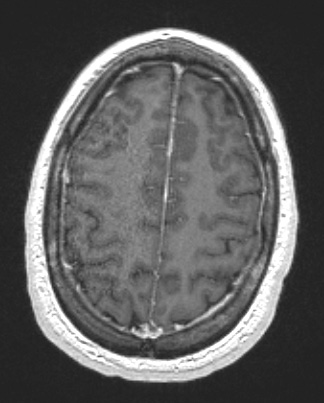

A T1-weighted contrast administered scan fails to show tumor enhancement.